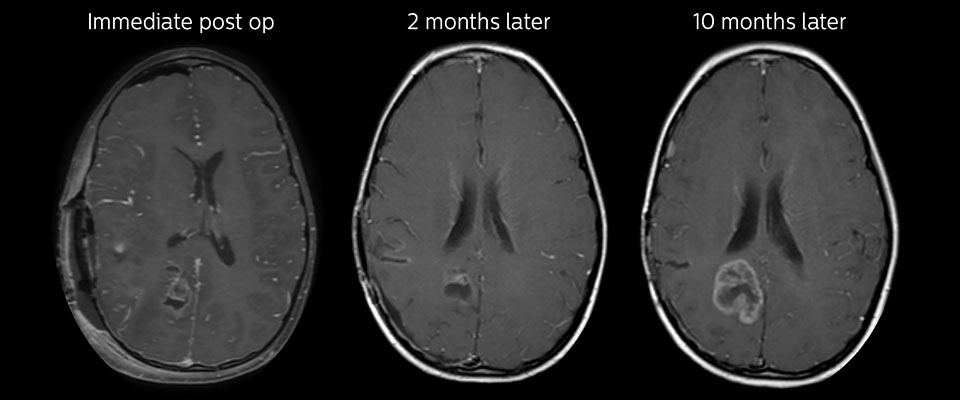

APT may illuminate post-resection images with crucial information

MRI may be performed after tumor resection, to look for residual tumor or tumor regrowth. Also here, the different contrast mechanism of APT may help in diagnosis. Dr. Miller remembers a particular case.

“After a very good resection, we saw small changes on the postcontrast T1-weighted and the T2-weighted images that looked like a post-surgical little bit of fluid. Interestingly, however, we saw a focal area of APT signal, right in the center of that abnormality. As we usually do when a bit unsure, we followed it up and, unfortunately, found tumor regrowth in that region,” Dr. Miller says. “Cases like this motivate me, and others who care about this population, to investigate how this APT method could be used on large scale in this population and help us in providing high value diagnostic information.”

The hospital’s physicians also saw a case where APT had a negative predictive value. Following the resection of a highgrade tumor, they saw a similar small change in the images of this patient. However in this case, the APT signal was rather low. In a recent rescanning of this patient, no recurrence was seen.

Follow-up over time results

Follow-up over time

In later follow-up scans the post-contrast T1-weighted images suggest recurrent tumor growth. So, it would be interesting to study the predictive value of APT in a large patient group.